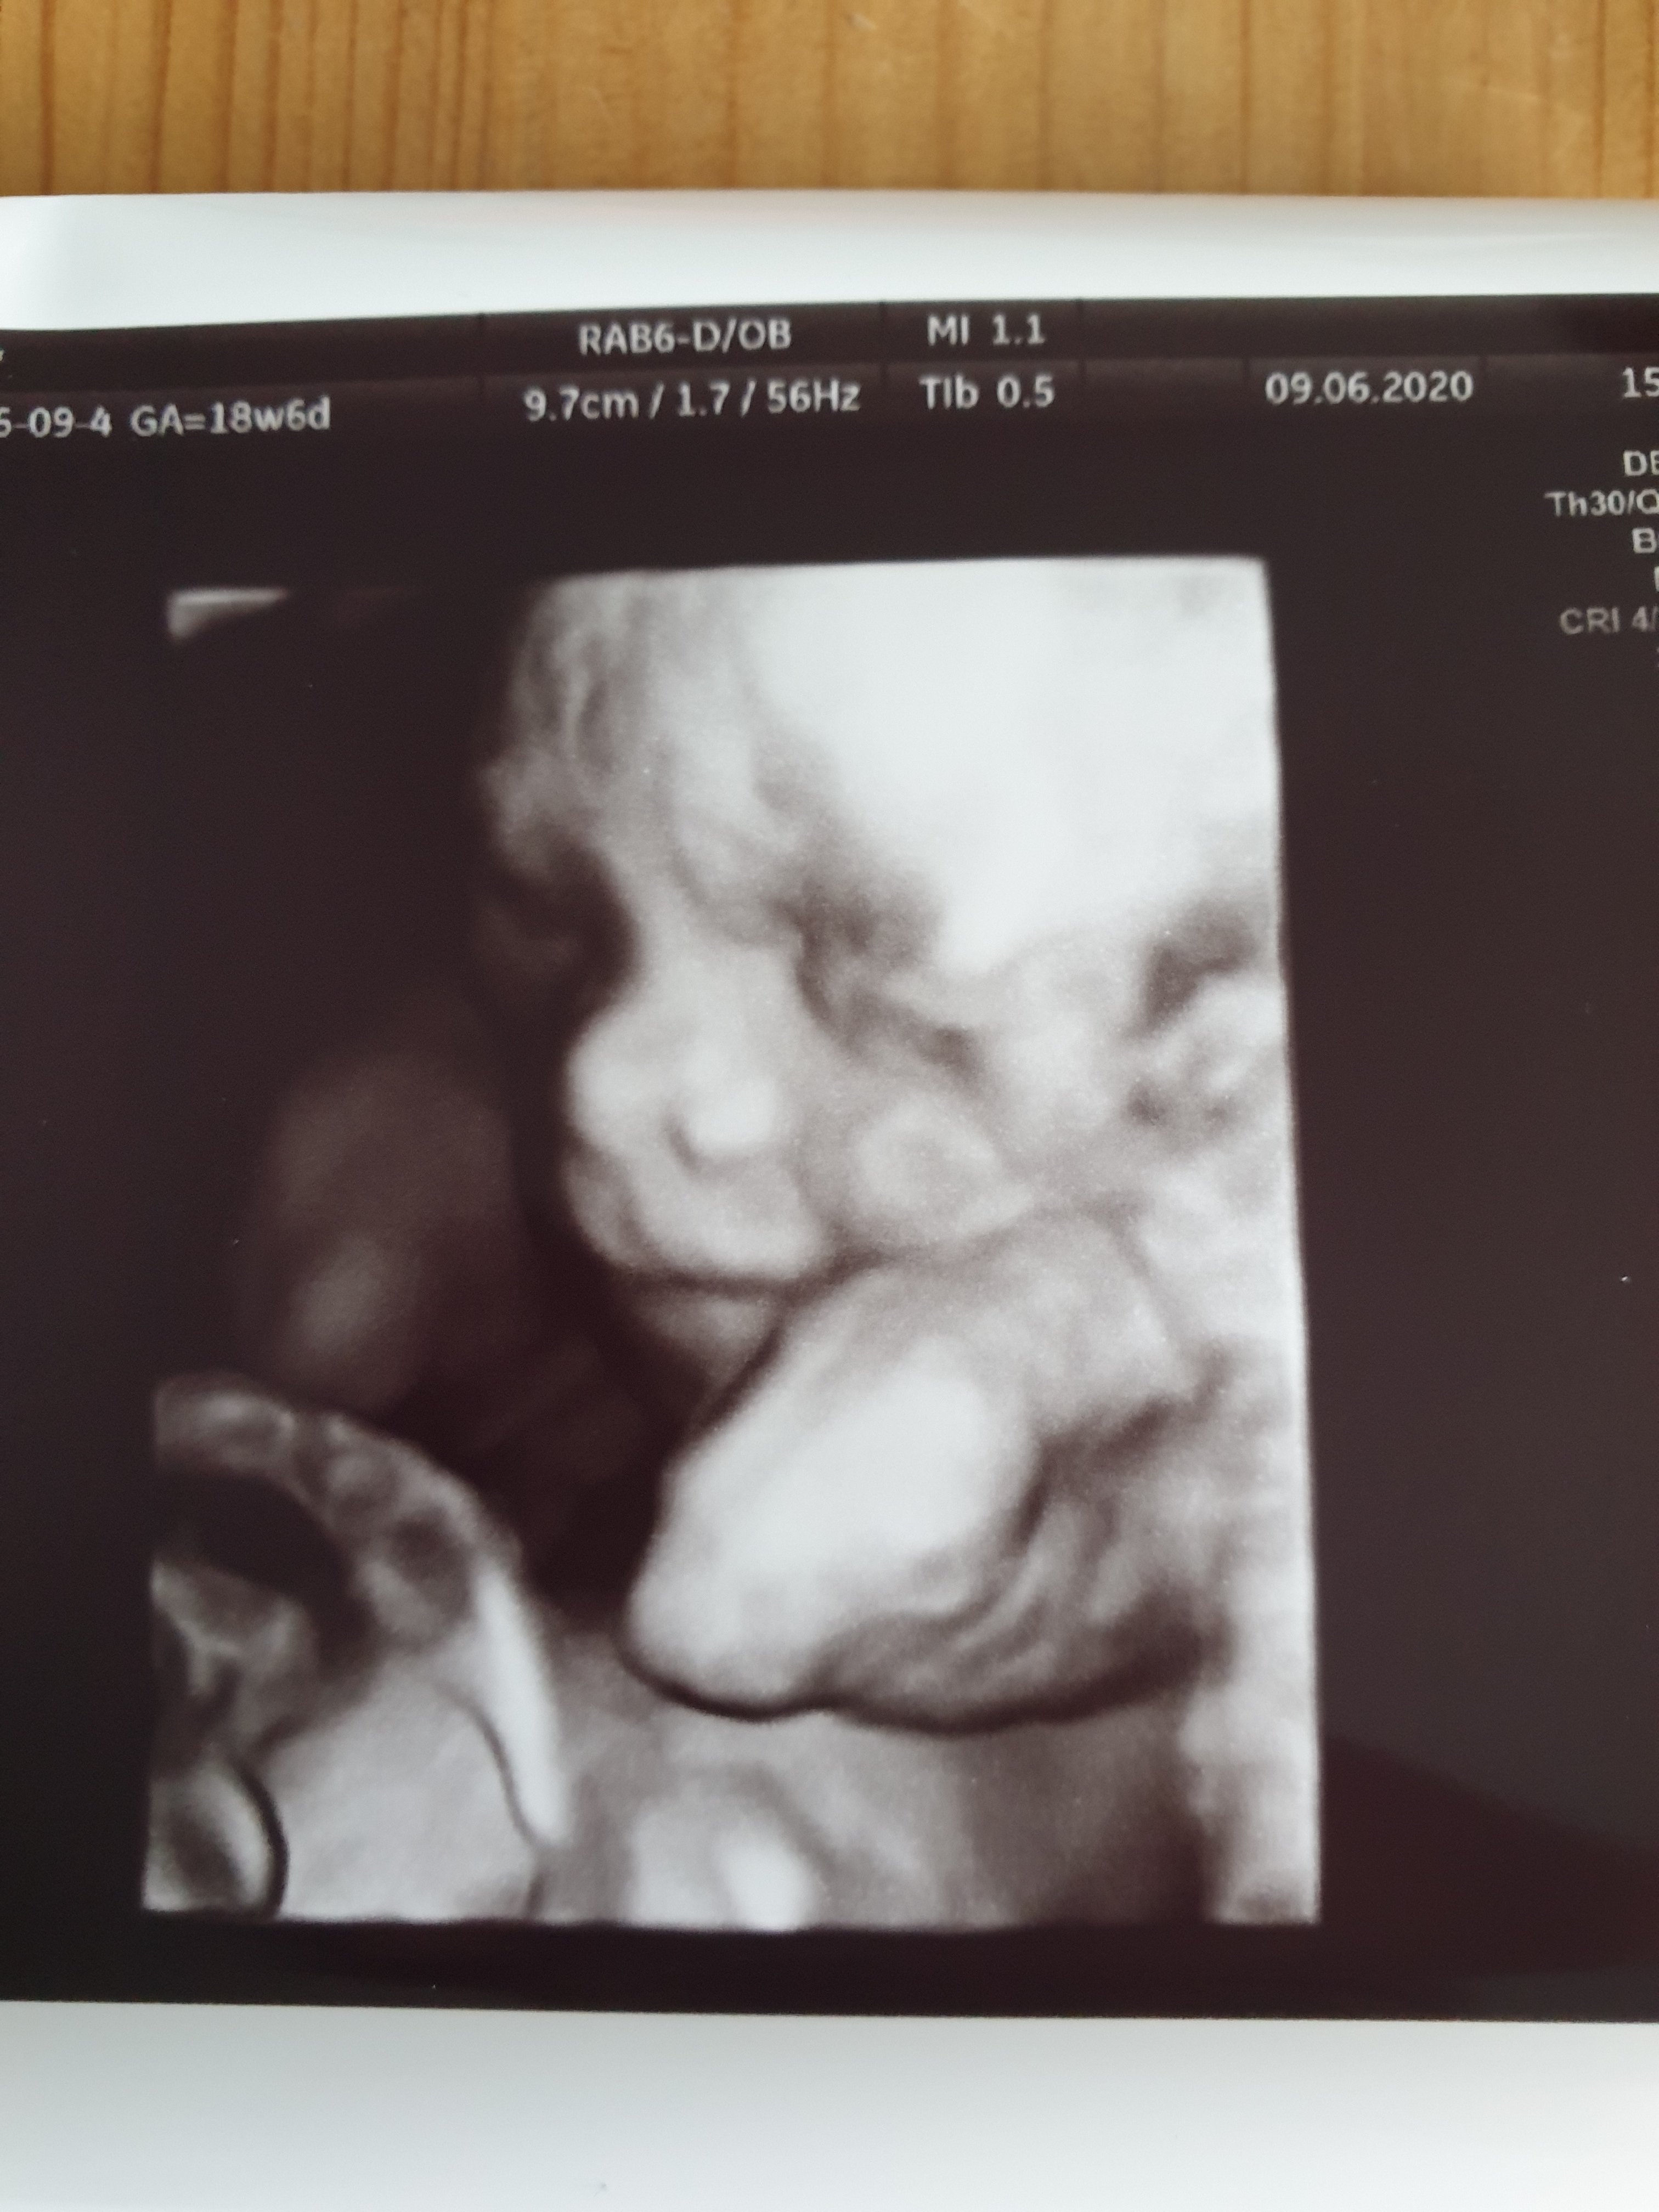

Cóż za cudny uśmiech !!!No to po wizyciechłopak na 100%

Mały troszke się uśmiecha![]()

Ale cudowny[emoji3059] mały przystojny śmieszek[emoji3531]No to po wizyciechłopak na 100%